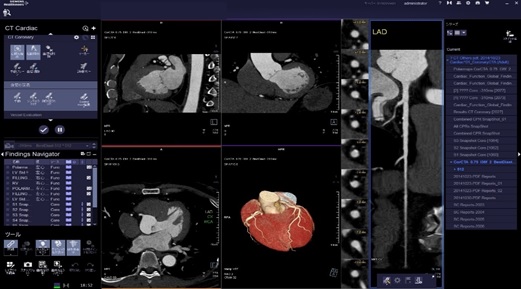

• 心臓CT(冠動脈CT)

当院の装置は管球1回転最速0.28秒と非常に早く、幅広い心拍の方に対応しています。

解析処理は専門のワークステーションを使用し、読影は循環器内科医師と画像診断専門医(遠隔画像診断支援)双方で行い、結果を循環器内科医師よりお伝えしています

心臓CT